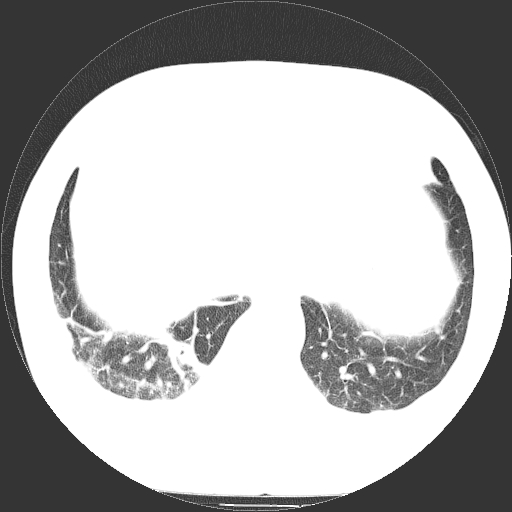

男,65岁,咳嗽、咳痰、发热5天。

慢支 肺间质纤维化合并感染!

支气管扩张合并感染,胸膜肥厚

考虑慢支并感染,肺间质纤维化。

两肺间质性炎症并感染

慢支,肺心病

支持慢性支气管炎伴感染,双侧少量胸腔积液.

两肺间质纤维化,支扩合并感染,双侧胸腔积液

感染,肺间质纤维化。

慢支 肺间质纤维化合并感染

支持慢性支气管、肺间质纤维化合并感染。

慢性支气管炎并感染,支扩,双侧少量胸腔积液.